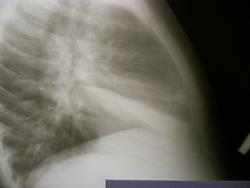

Первые 2 снимка сегодня, вторые 2 майские.

Написал бы р-признаки ателектаза средней доли правого легкого. Если есть возможность, сделал бы снимки по Флейшнеру.

Кстати, видите, как неправильно ограничиваться только прямыми снимками.